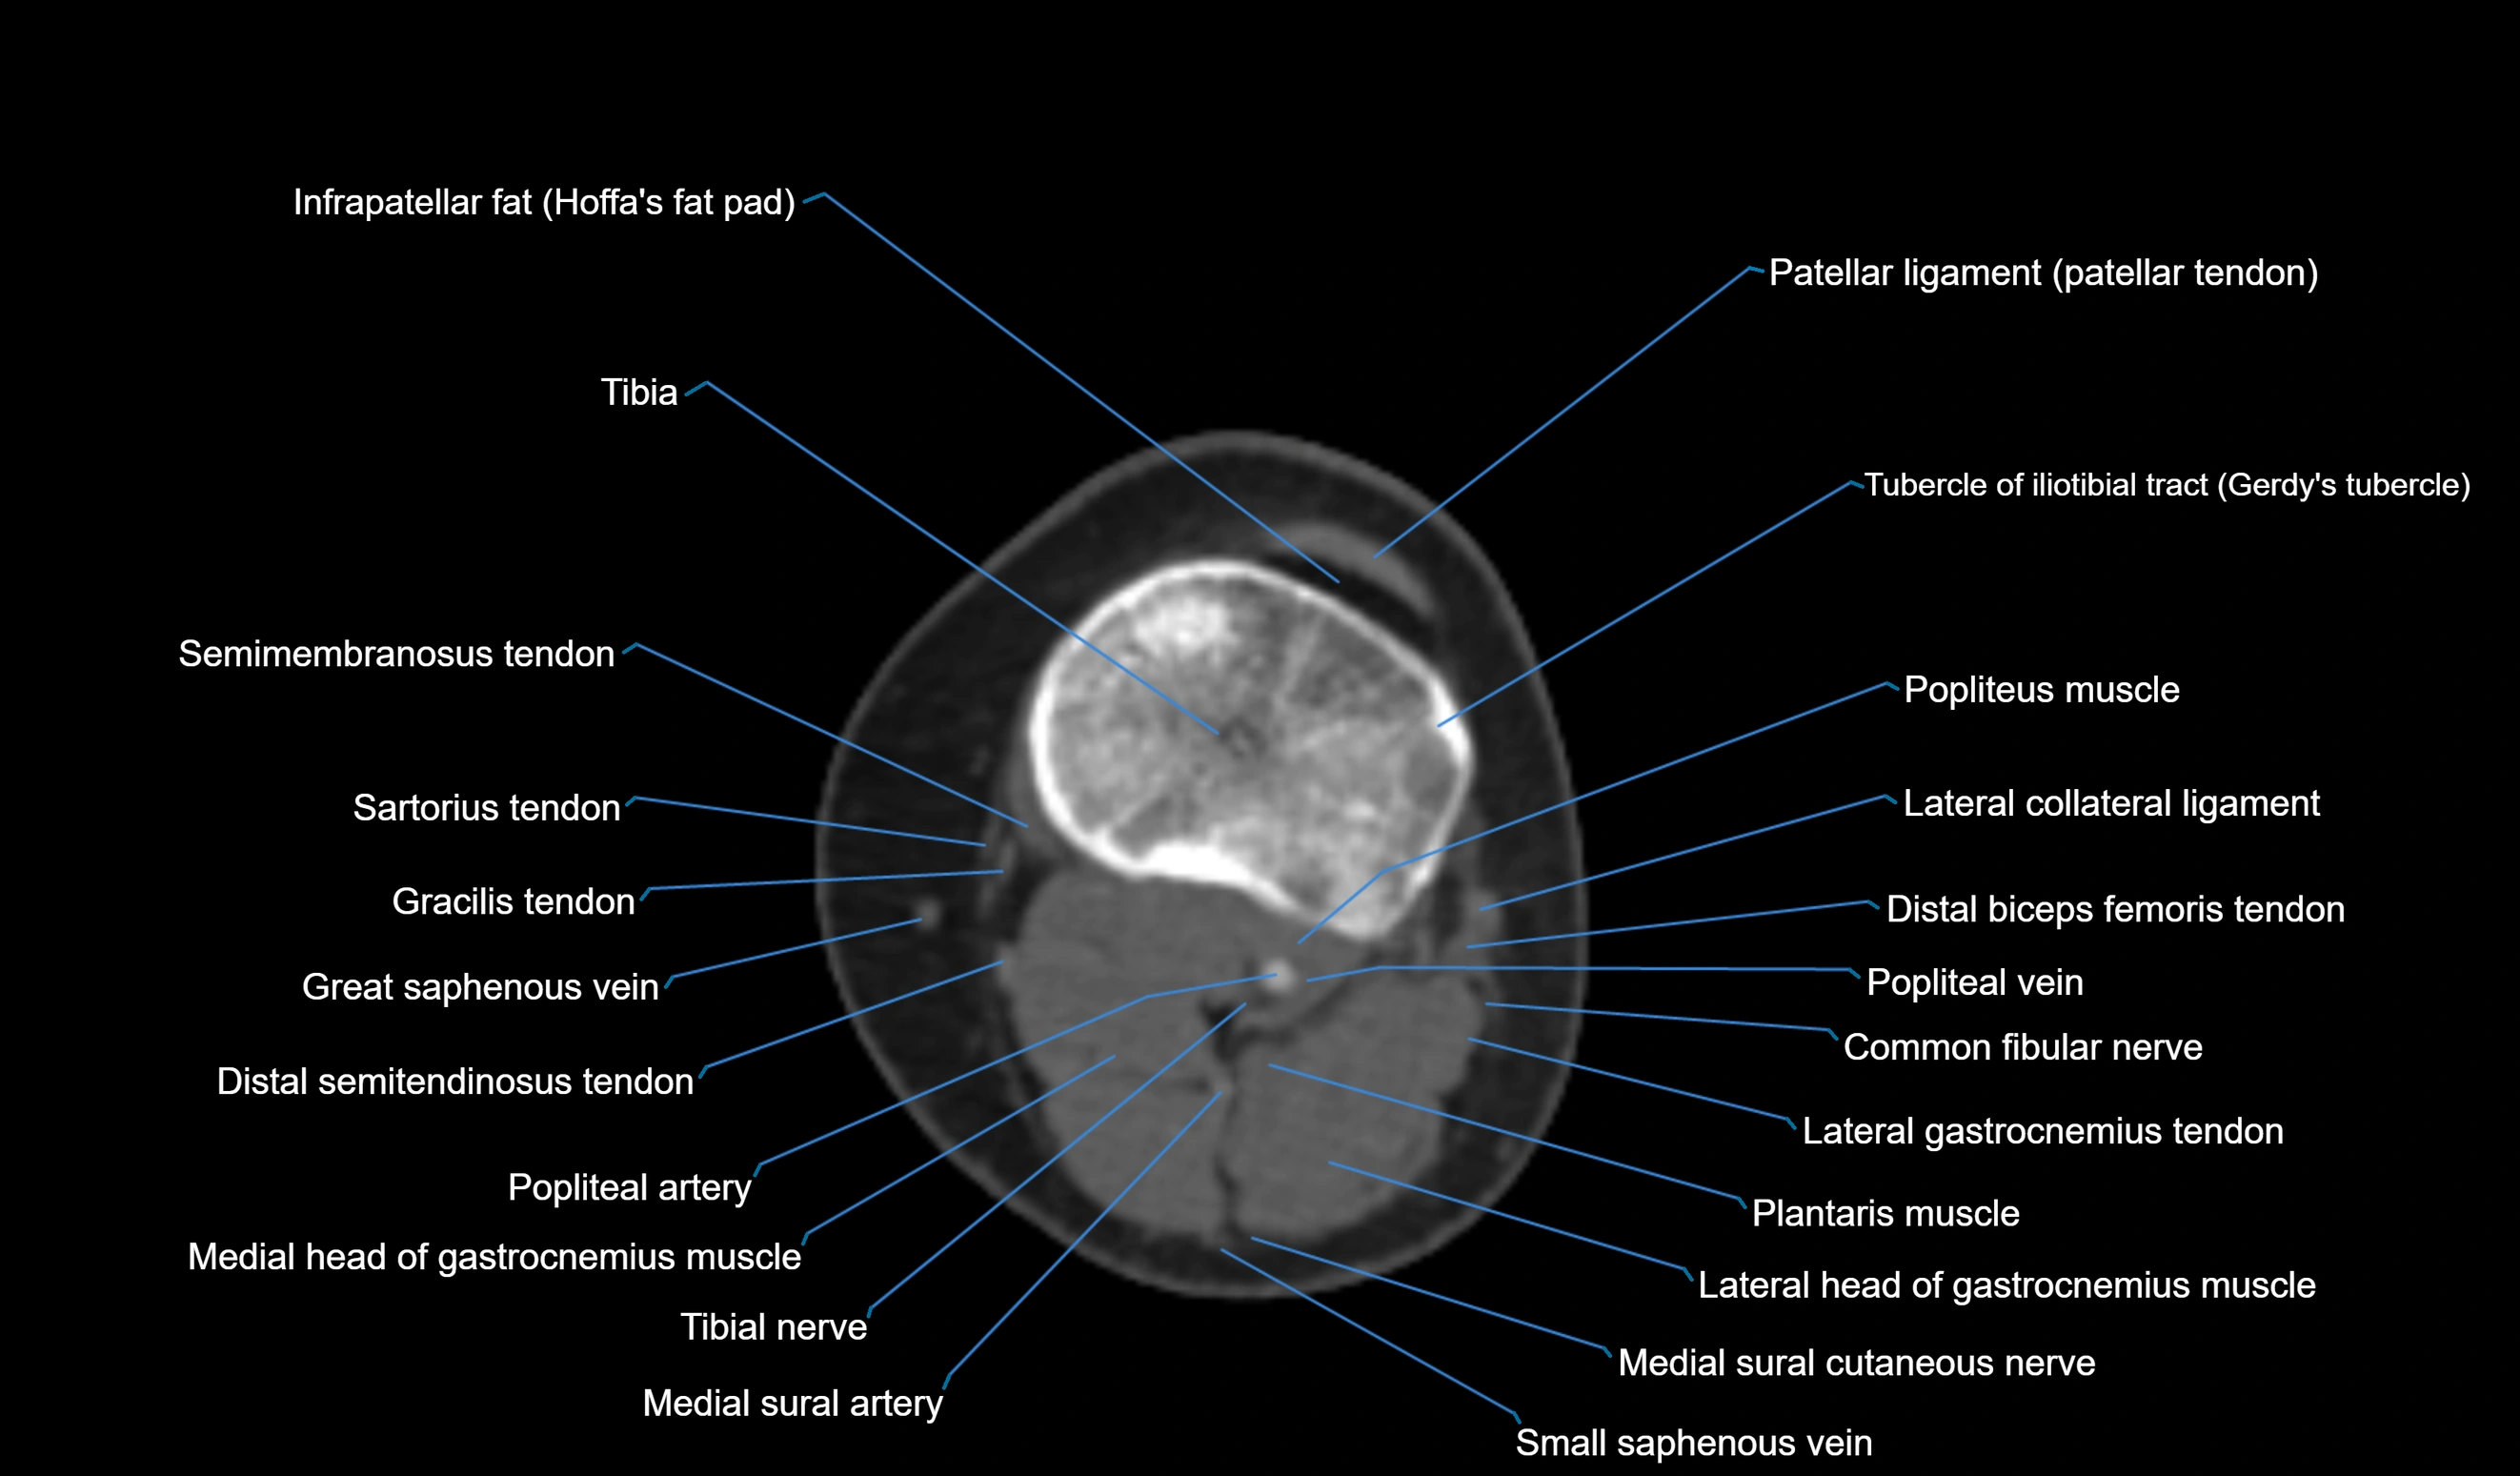

- Common fibular nerve

- Gracilis tendon (Distal)

- Infrapatellar fat pad

- Lateral collateral ligament

- Lateral gastrocnemius tendon

- Lateral head of gastrocnemius muscle

- Medial head of gastrocnemius muscle

- Medial sural cutaneous nerve

- Patellar tendon (patellar ligament)

- Plantaris muscle

- Popliteal artery

- Popliteal vein

- Popliteus muscle

- Sartorius tendon (Distal)

- Semimembranosus muscle

- Small saphenous vein

- Tibia

- Tibial nerve

- Tubercle of iliotibial tract

- great saphenous vein